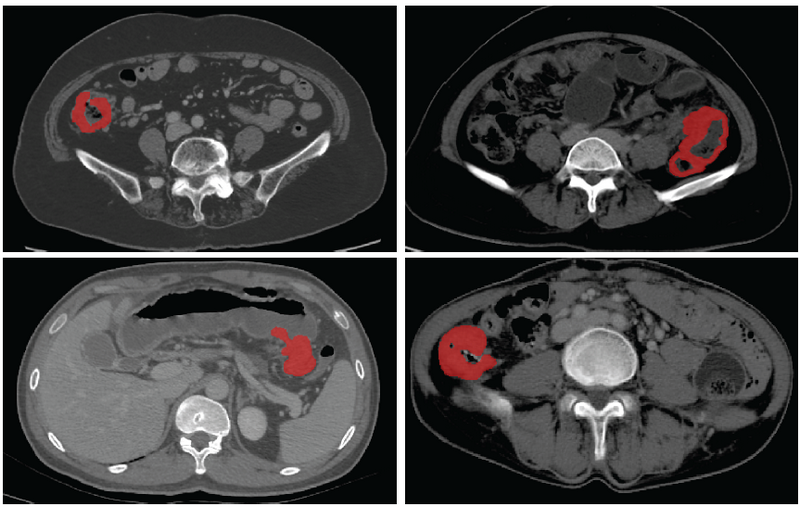

基于CT影像的结肠癌病灶分割

据介绍,基于医学影像的人工智能为肠癌个体化诊疗提供了巨大的可能性,已经有多项研究实现了病人的疗效预测、术后复发风险评估,但这些应用无不依赖于精准的病灶分割。此次SOUSA技术的开发在国际上首次实现了结肠癌的自动分割,为加速肠癌人工智能精准诊疗的临床应用奠定了基础。自动化标准化的精准影像信息处理将有效地降低经济、时间和人力成本,为精准诊疗的实施提供了重要的临床依据,具备极大的临床转化应用前景。

团队利用来自best365中国官方网站附属第六医院和喀地一院的923例有标注结肠癌CT影像和2670例无标注结肠癌CT影像作为SOUSA框架的训练数据集,并利用417例结肠癌CT影像对SOUSA框架进行验证,结果显示其自动分割效果优于现有的弱监督和半监督学习模型。与目前最先进的方法ICT (Verma et al.,2019)、不确定性感知(Yu et al.,2019)和自我训练相比,SOUSA框架在每个数据比率上都达到了最佳性能。此外,当数据集的大小有限时,SOUSA框架的性能甚至与使用密集注释的模型的性能相当。